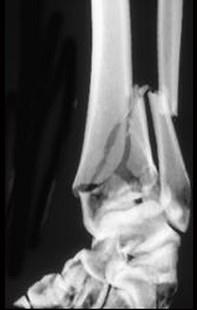

问题 男,45岁,车祸后10小时,请结合影像学检查,选出最可能的诊断 ( )

选项 A、柯莱斯骨折 B、加莱阿齐骨折 C、尺桡骨骨折 D、蒙泰贾骨折 E、胫腓骨骨折

答案 E